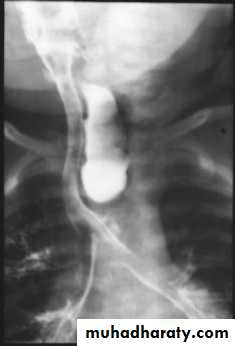

-- Barium study

Blind end esophageal pouch = pooled secretion.Fistulous connection with trachea = aspiration.

Presentation :-Polyhydraminous.Frothy secretion.Respiratory distress.Resistance to NG tube insertion.Plain X-ray.